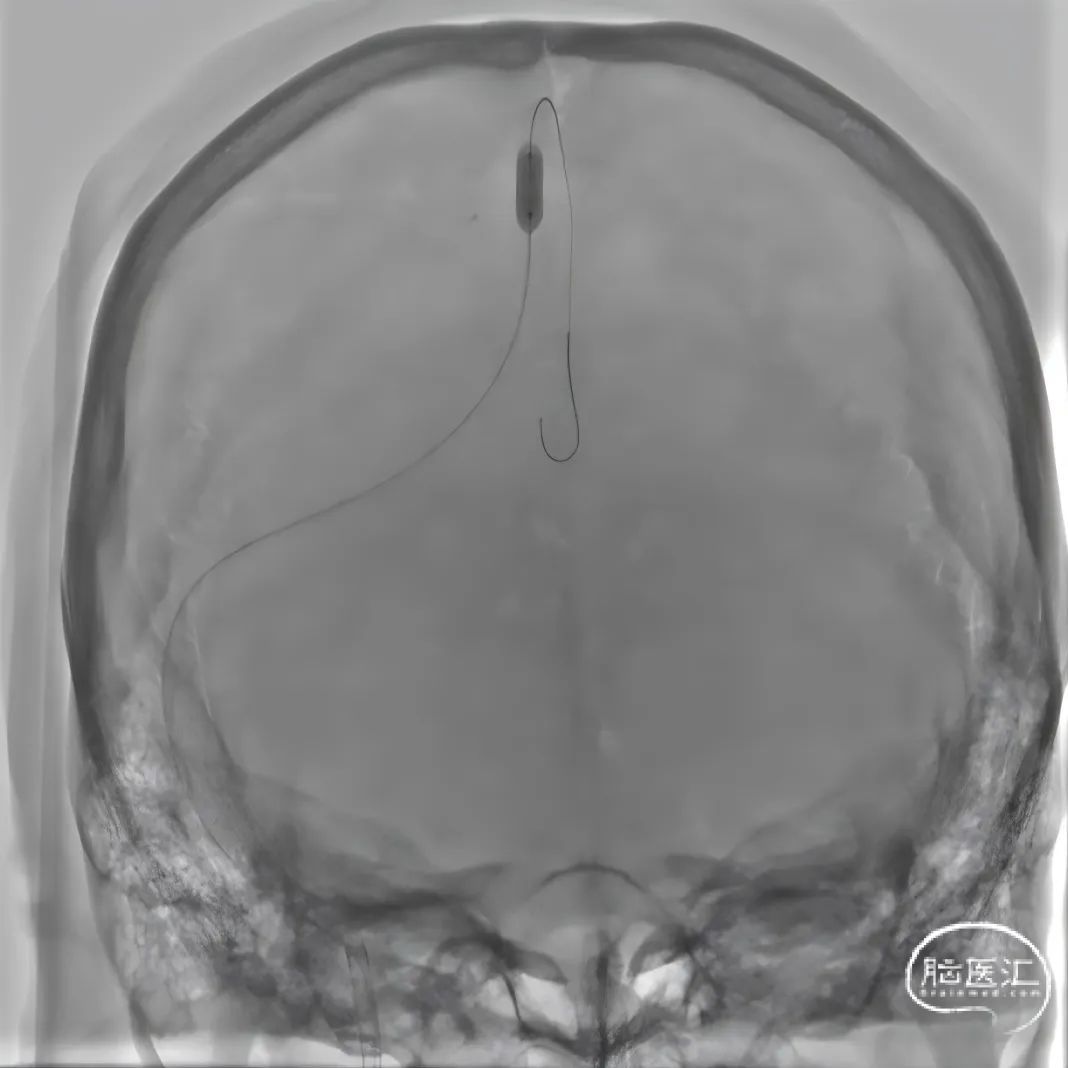

股动脉穿刺置5F鞘做静脉窦造影,股静脉穿刺置8F鞘进行治疗。260cm泥鳅导丝,将132cm 0.068" React™导管送至上矢状窦前部,尽量推高长鞘,增加支撑力。

经中间管手推造影,确认血栓位置。

反复抽吸,多次中间管于负压状态下无回血时,负压状态撤出体外,可见大量血栓。

单纯抽吸难以实现良好再通,经300cm微导丝长交换送入115cm Navien™颅内支撑导管;选用5*30mm球囊扩张,碎栓。

留置Rebar™ 27微导管,持续尿激酶接触溶栓(配比浓度1万U/ml,8ml/h持续泵入)。